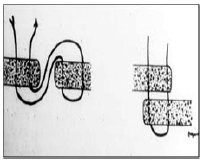

Nas suturas interrompidas os fios são fixados separadamente, podendo variar a tensão de acordo com a necessidade em cada ponto. É considerada mais segura, já que o rompimento de um ponto não inviabiliza a sutura toda. É menos isquemiante, confere maior permeabilidade à ferida e consegue força tensil maior e de modo mais rápido. Como desvantagens, possui uma elaboração mais lenta e trabalhosa. Relacione os tipos de sutura com as imagens e assinale a alternativa que apresenta a ordem correta.

1. Sutura em Jaquetão.

2. Sutura em “X” ou Sultan.

3. Sutura de Mayo.

4. Sutura de Halsted.